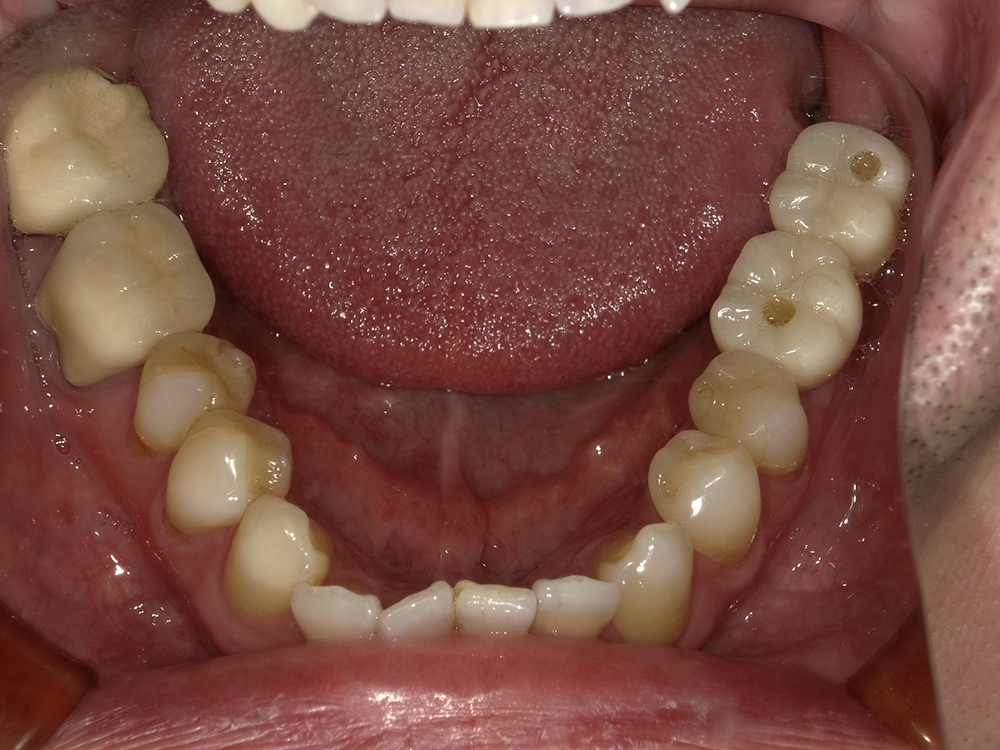

53歳 男性

- 主訴

- 全然噛めない。上の歯が取れてきた

- 処置内容

- 上顎:8本 下顎:2本

- 治療費用

- 上顎:約320万円(税込)、下顎:約160万円(税込)

- 治療期間

-

上顎:1年(仮歯まで8か月)

下顎:8か月(仮歯まで5か月)

- リスク

- 上部構造物、仮歯の破折、術後の腫れ(3日)、人工歯根脱落リスクがあります